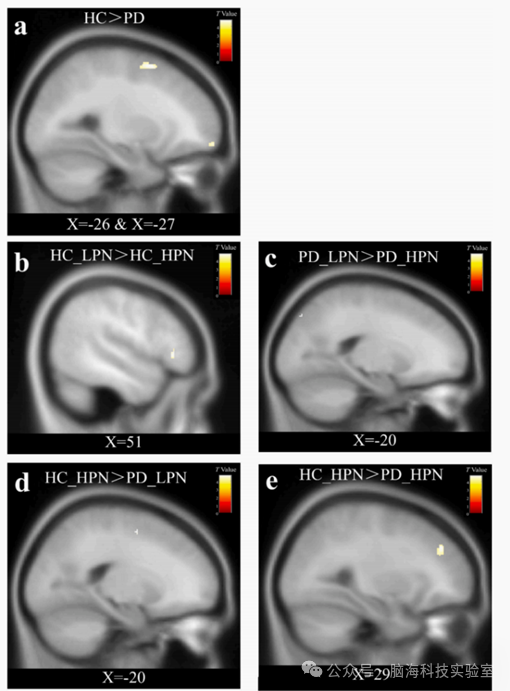

HC组相比,发现PD患者在左中额回和左中额回眼眶部分的GMV显著降低(见表3,图1a)。在亚组比较中,与HC_LPN相比,HC_HPNPD_HPN均显著降低GMV,特别是右下额回三角区域HC_HPN前额PD_HPN见表31b1c)。与HC_HPN患者相比,PD_LPN患者左上额回GMV显著降低,而PD_HPN患者右中额回的GMV显著下降。

图片

3.组间GMV比较

1.g PD_HCT, PD_LCT, HC_HCT and HC_LCTGMV比较

本研究首次系统探讨了童年身体忽视对惊恐障碍患者脑灰质体积的特异性影响,以及这种影响与临床症状严重程度的关系。研究结果表明,与健康对照相比,惊恐障碍患者在左中额回及其眶部区域灰质体积显著减少。这一发现与先前研究一致,表明前额叶皮层的结构异常可能是惊恐障碍的核心神经生物学特征。前额叶作为恐惧调控网络的关键节点,其灰质减少可能损害自上而下的恐惧抑制功能,导致无法有效调节来自杏仁核的恐惧信号,从而促进惊恐发作的发生与维持。

研究表明,那些经历高程度身体忽视却未发展出精神障碍的健康个体(HC_HPN)在右前额叶区域显示出更大的灰质体积,特别是与惊恐障碍患者相比。这一结果强烈暗示,前额叶皮层的增大可能作为一种神经保护机制,帮助某些个体抵抗童年逆境的负面影响。这一发现为理解心理韧性的神经生物学基础提供了新视角,表明大脑可能发展出补偿性机制来应对早期环境压力。